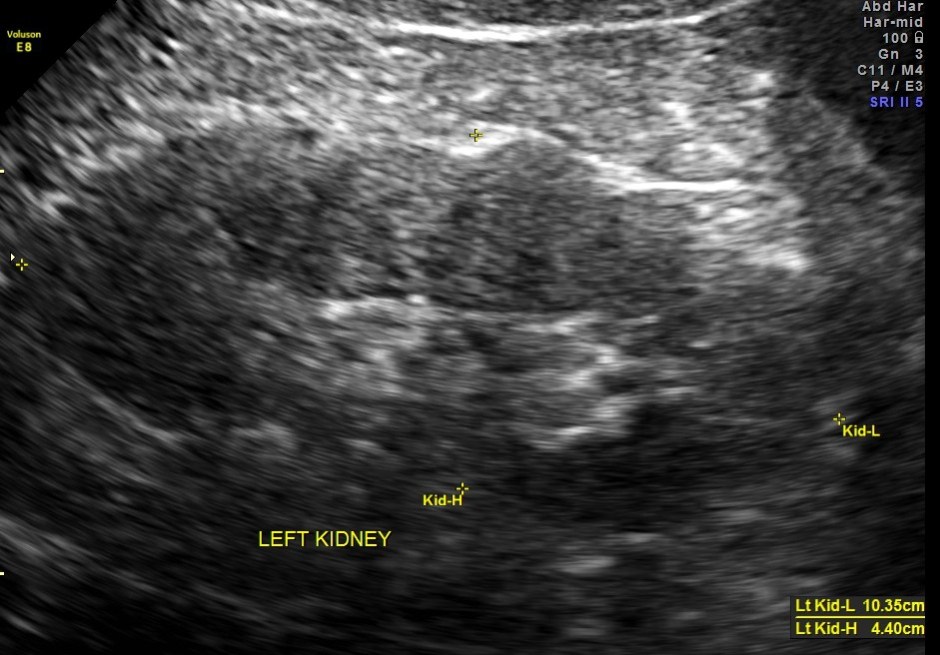

This was a 57 year old gentleman , with complaints of difficulty in passing urine and dysuria of 1 month duration.

His upper abdominal scan was normal . His left kidney was normal.